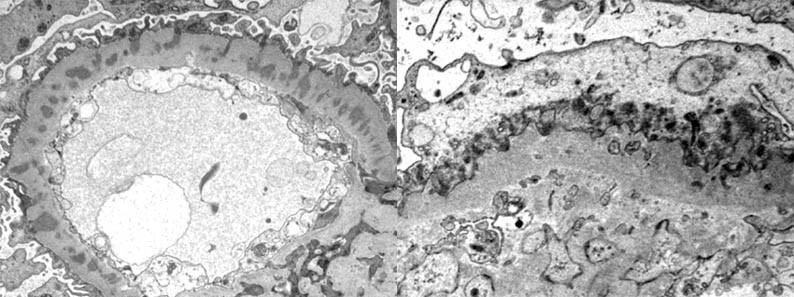

Minimal Change Disease

EM – Microvillous Transformation

– Effaced Foot Processes

■ Correct Answer (B): Extensive foot process effacement is the characteristic EM finding in minimal change disease (MCD), which is the most common cause of nephrotic syndrome in children and has normal or near-normal glomeruli under light microscopy.